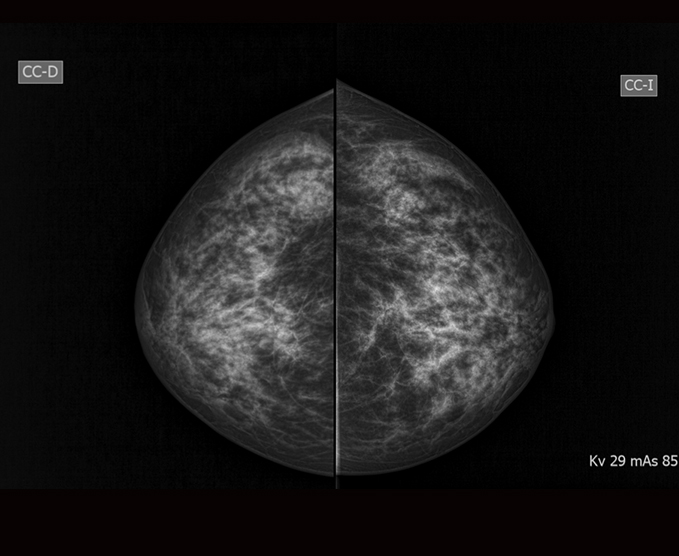

Es una exploración específica para el seno, que se realiza a través de rayos X. En mujeres mayores de 40 años se utiliza generalmente para buscar signos precoces de cáncer de seno. Los expertos coinciden en que el éxito del tratamiento de esta enfermedad va unido al diagnostico temprano, en lo cual la mamografía tiene una importancia determinante.

Cada seno se coloca en un soporte perpendicular al tubo de rayos X del Mamógrafo y se realiza una comprensión sobre el mismo; esta comprensión pudiera generar alguna molestia, pero es indispensable para obtener una imagen nítida de los tejidos. El haz de rayos X atraviesa el seno y la imagen de este se imprime en una película radiográfica, o es enviada a un monitor para ser estudiada por el médico radiólogo.